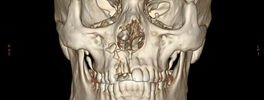

3D CT Facial Bones